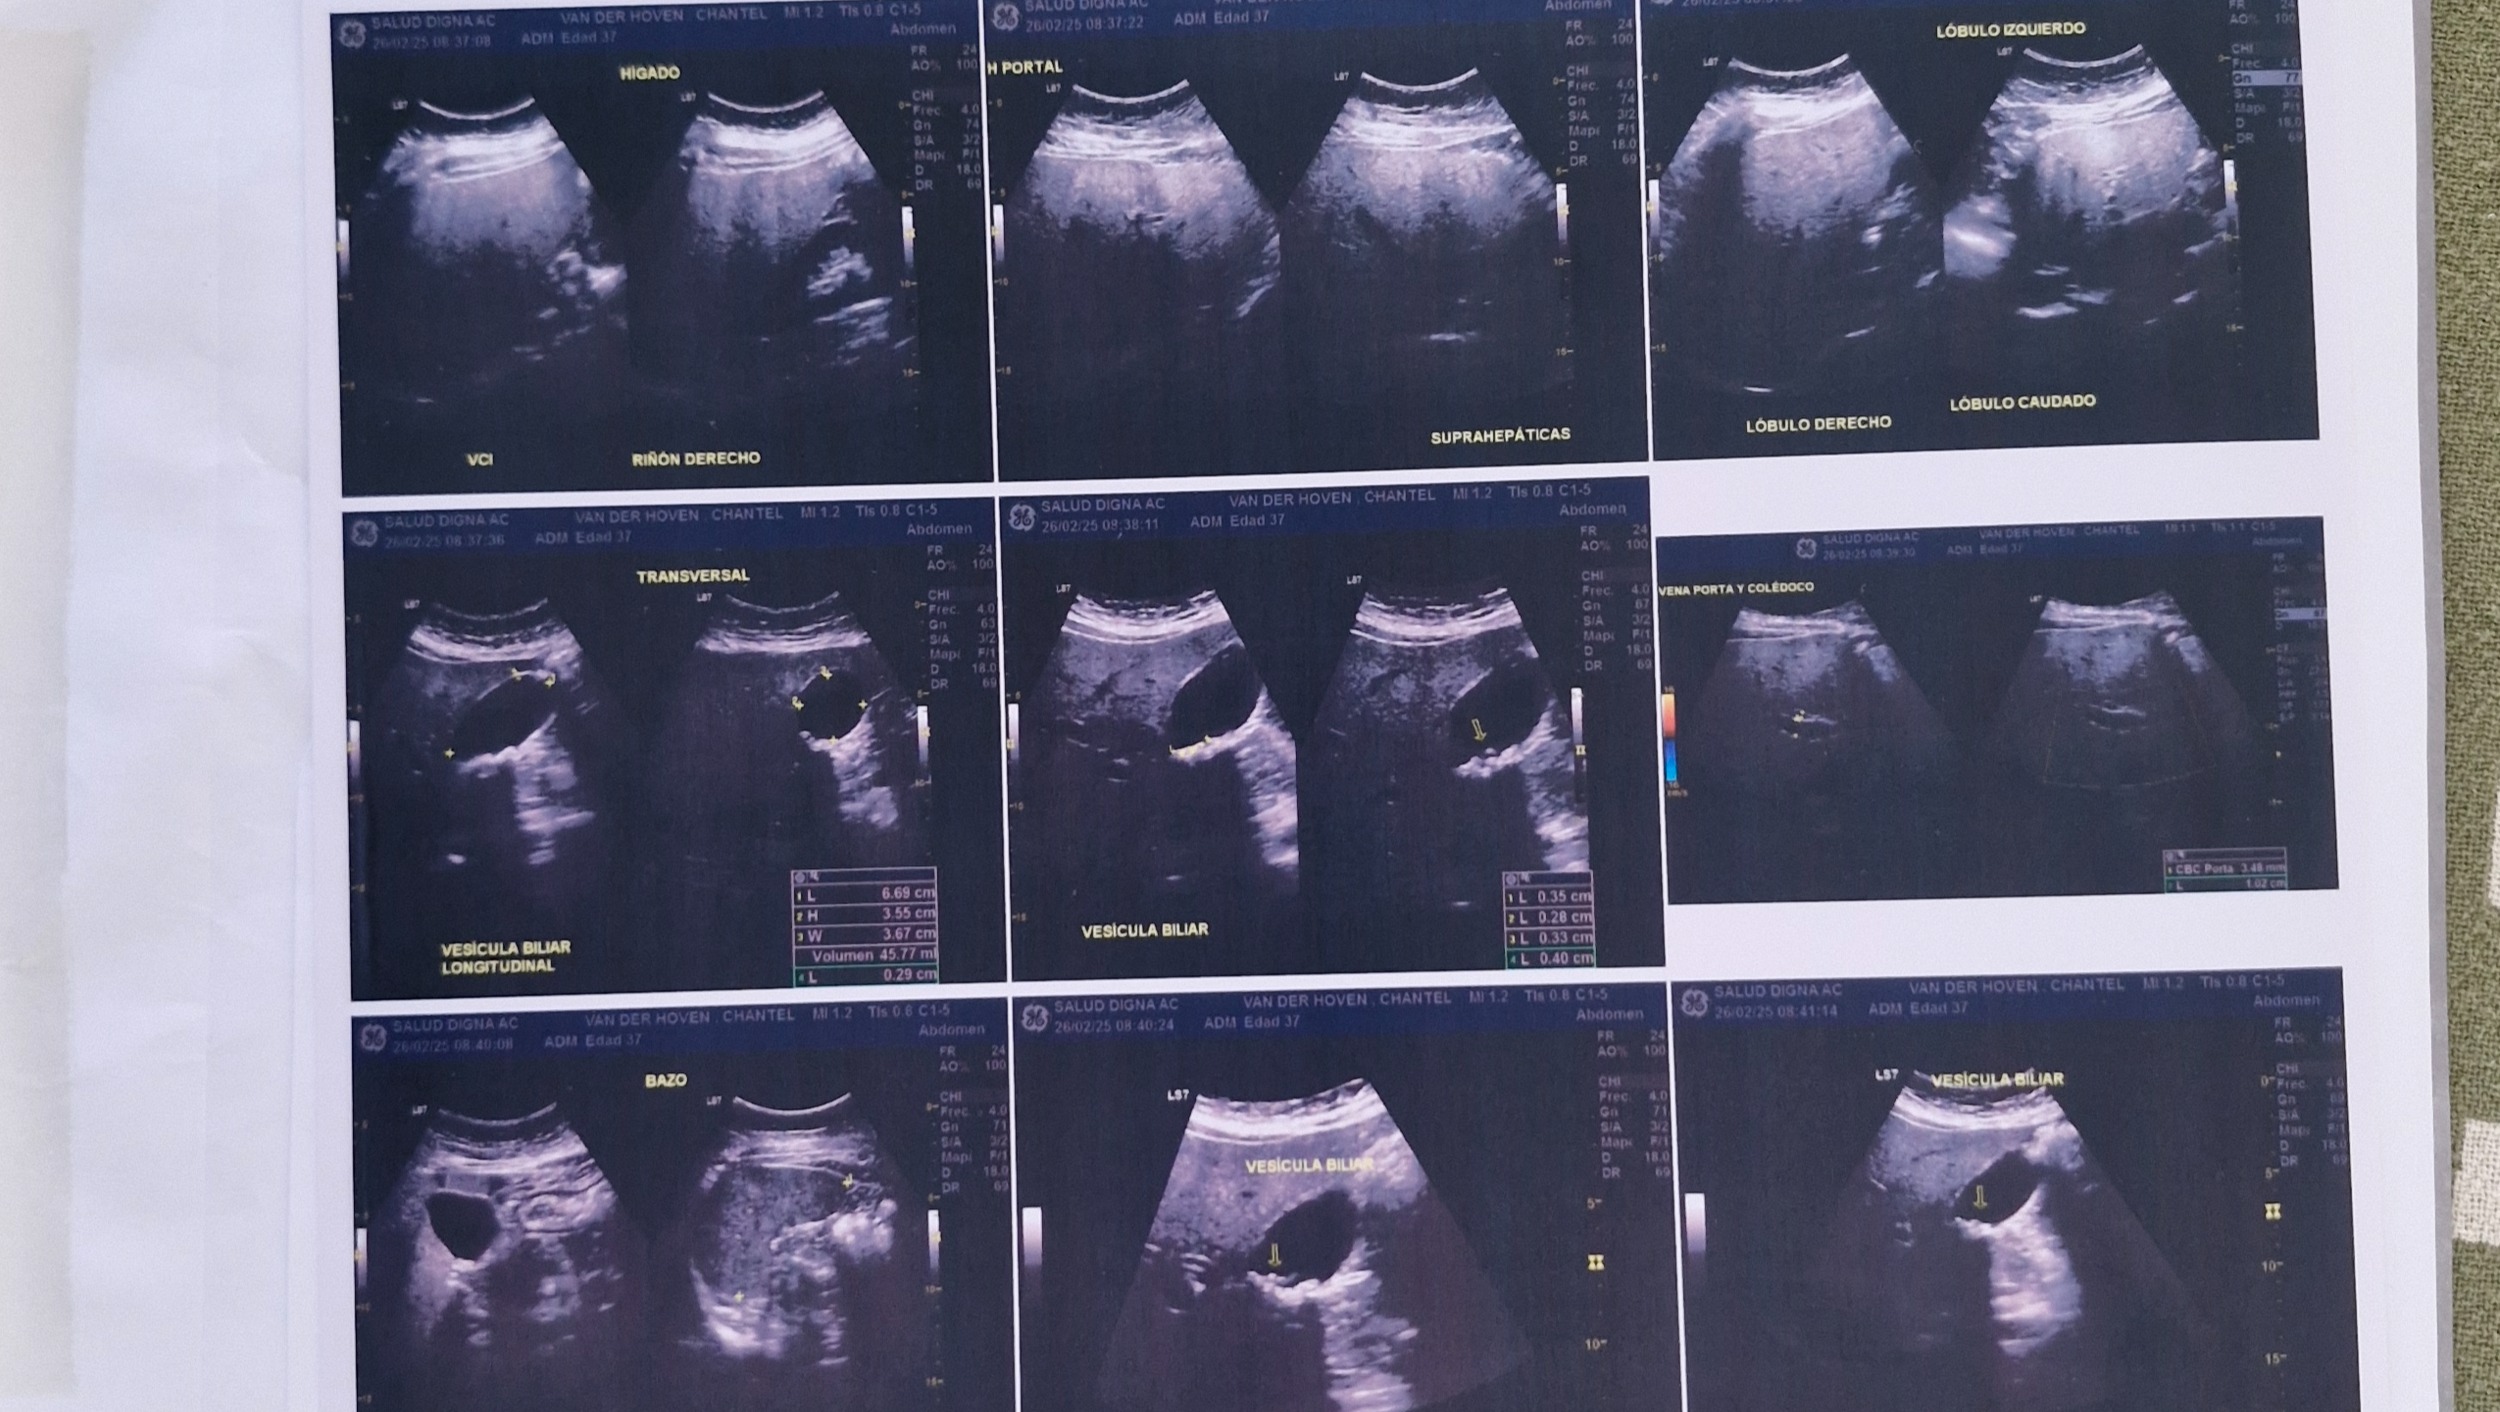

Hola, hace un mes chantel presento mucho dolor en la boca del estomago y esta semana decidimos ir al doctor por lo cual nos envio a hacer estudios en donde aparecieron 7 piedras en la vesicula por lo que se necesita una cirujia lapararoscopia por lo cual estamos pidiendo de tu apoyo de los gastos de la cirujia. muchas gracias bendiciones

Hello, a month ago Chantel had a lot of pain her stomach and this week we decided to go to the doctor. The ultrasound showed 7 stones in her gallbladder. So the laparoscopic surgery is needed and this has been scheduled for Monday the 3rd of March. The surgery costs are 40,000 pesos and we just dont have the funds for this and so this is the reason we have started this Gofundme account asking for support to cover the surgery costs. Chantel has peace and knows the Lord is with her and that He can provide for more than what we can ask for. Thank you very much, blessings.